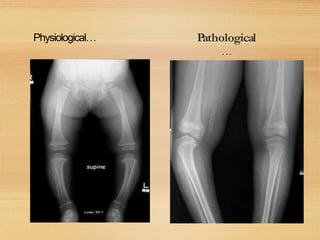

Physiological… Pathological

…

In ligamentous laxity notelat.Widening

Of knee joints

In Blount angulation at med.tib

metaphysis

In coxavara ,angulation at the neck shaft

level

In cong. Pseudarthrosis of tibia,the

angulation is in the distal⅓